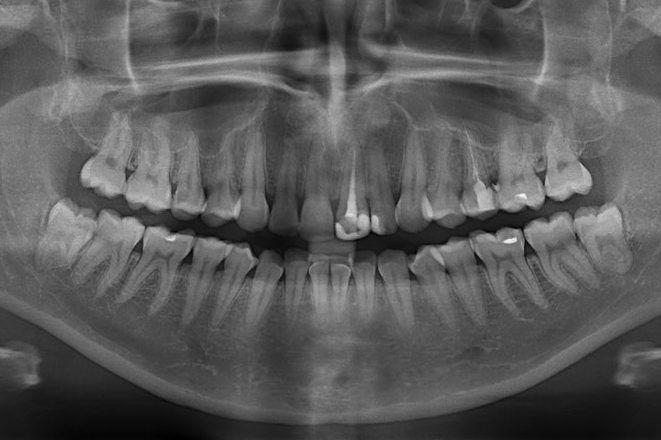

Рентгенологический снимок всей зубочелюстной системы.

На первичной консультации во время беседы мы выясняем проблемы, запросы и пожелания пациента. В обязательном порядке после осмотра проводим диагностику, чтобы получить всю необходимую информацию о состоянии зубов. Мы составляем фотопротокол. Фотографии позволяют детально изучить проблемные зоны, а пациенту – наглядно увидеть проблемы. В дальнейшем можно легко оценить результаты до и после.